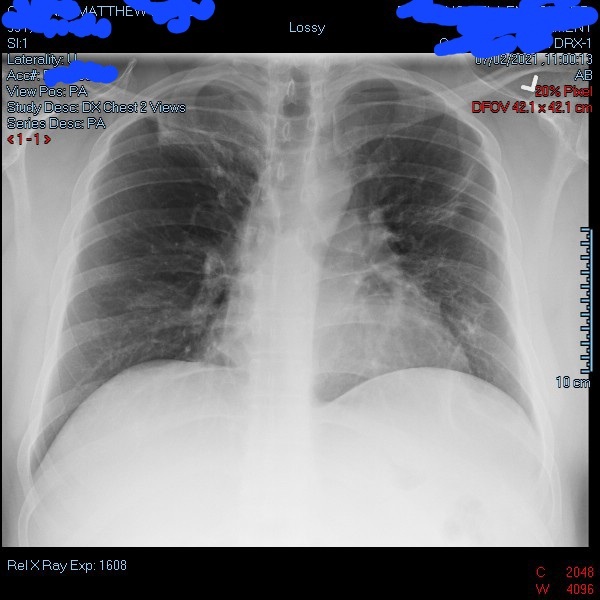

This image was taken months after Cardinal was discharged from the hospital following his recovery from COVID-19. This X-ray shows his lungs do not have as much of a cloudy look to them compared to X-rays taken when he was admitted to hospital on March 22, 2021.

This image was taken months after Cardinal was discharged from the hospital following his recovery from COVID-19. This X-ray shows his lungs do not have as much of a cloudy look to them compared to X-rays taken when he was admitted to hospital on March 22, 2021. Courtesy: Matthew Cardinal

“My lungs are still pretty cloudy and they’re starting to think it’s scar tissue – damage from extreme pneumonia,” Cardinal discussed. “About a year later, I’m still dealing with shortness of breath. I can’t really run. I can walk fast, but I can’t do it (again) for like a whole day because it really takes it out of me.”

Cardinal admitted it was difficult to see how much his lungs have changed since he was infected with COVID-19.